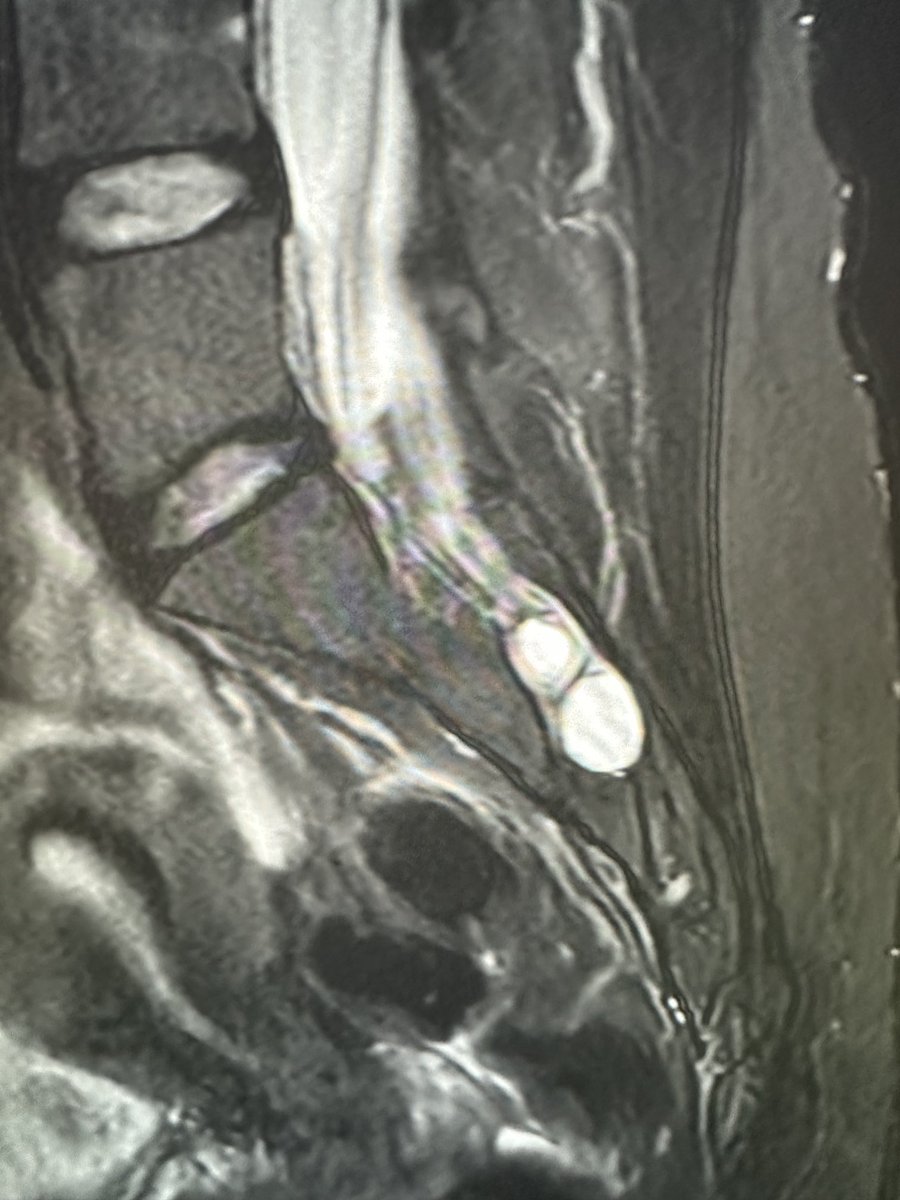

Young RHD pt in MVC with R shoulder dislocation and large cuff avulsion. Also w/ a DENSE brachial plexopathy with no motor or sensation below the deltoid. Axillary n. is ok. Everything distal to that is out. Plexus MRI shows edema w intact plexus Haven’t seen this in a bit